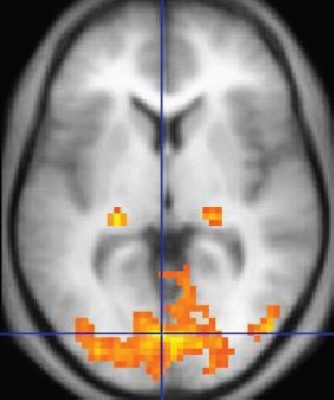

Azoknál, akik hallják és megértik a verbális utasításokat, de nem reagálnak azokra, a második réteg azt jelenti, hogy megfigyelik, mi történik az agyukban az utasítás fogadását követően, ahogyan az a 2005-ös kísérletben részt vevő nő esetében történt. „Ha olyan agyi aktivitást találunk, amely specifikus az adott aktív feladatra, például a teniszjátékhoz kapcsolódó premotoros kéreg aktivitására, az ugyanolyan jó indikátora a tudat jelenlétének, mint a kéz megszorítása” – mondja Massimini. Ezeket a betegeket kognitív motoros disszociációval, egyfajta rejtett tudattal rendelkezőként azonosítják.

Egy 2017-es tanulmányban a kutatók egy 24 másodperces részletet játszottak le John F. Kennedy amerikai elnök beiktatási beszédéből olyan embereknek, akik súlyos, traumás agysérülést szenvedtek. A hangfelvételt visszafelé is lejátszották nekik. A két felvétel akusztikai jellemzői hasonlóak voltak, de csak az elsőnél várták a nyelvi feldolgozás beindulását az agyukban; a második kontrollként szolgált. Az fMRI segítségével a kísérlet négy olyan személynél segített kimutatni a rejtett tudatot, akik egyébként nem mutatták nyelvértés jeleit.

Az ilyen megközelítés laboratóriumi környezeten kívüli megvalósításának összetettsége nem az egyetlen kihívás. E tesztek megkövetelik a kutatóktól, hogy tudják, mely agyi aktivitási minták tükrözik valóban a tudatot, mert egyes ingerek tudat nélkül is kiválthatnak agyi reakciókat. A lényeg az tehát, hogy megértsék, mik a tudatos észlelés idegi összefüggései.